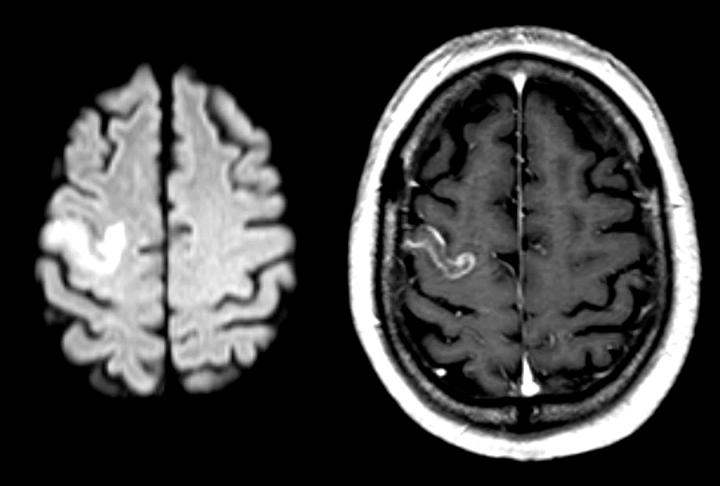

The article deals with a study, carried out in Germany, observing a group of stroke patients with language difficulties. They were all brain scanned using the fMRI technique as an important part of the analysis. An essential part of the research was done by the Bergen fMRI Group at UiB.

The patients were scanned several times by an fMRI-machine, both before and during language training. During a multimodal analysis, the researchers studied how the networks of the brain were activated.

The multimodal analysis involves analysing MR scan images of the extent of the brain damage in stroke patients whilst studying brain activity using fMRI scans.

"Using this method, it is possible to find the localisation of the damage, the size of the damage and how the activation patterns in the neural networks are related," Specht explains.